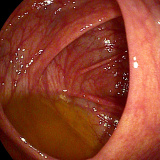

Enfermedades relacionadas con el intestino grueso

-

Diverticulosis colónica

Colitis ulcerosa

Enfermedad de Crohn

Colitis microscópica

Colitis isquémica

Pólipos colónicos

Cáncer de colon

Cribado poblacional o familiar de cáncer de colon